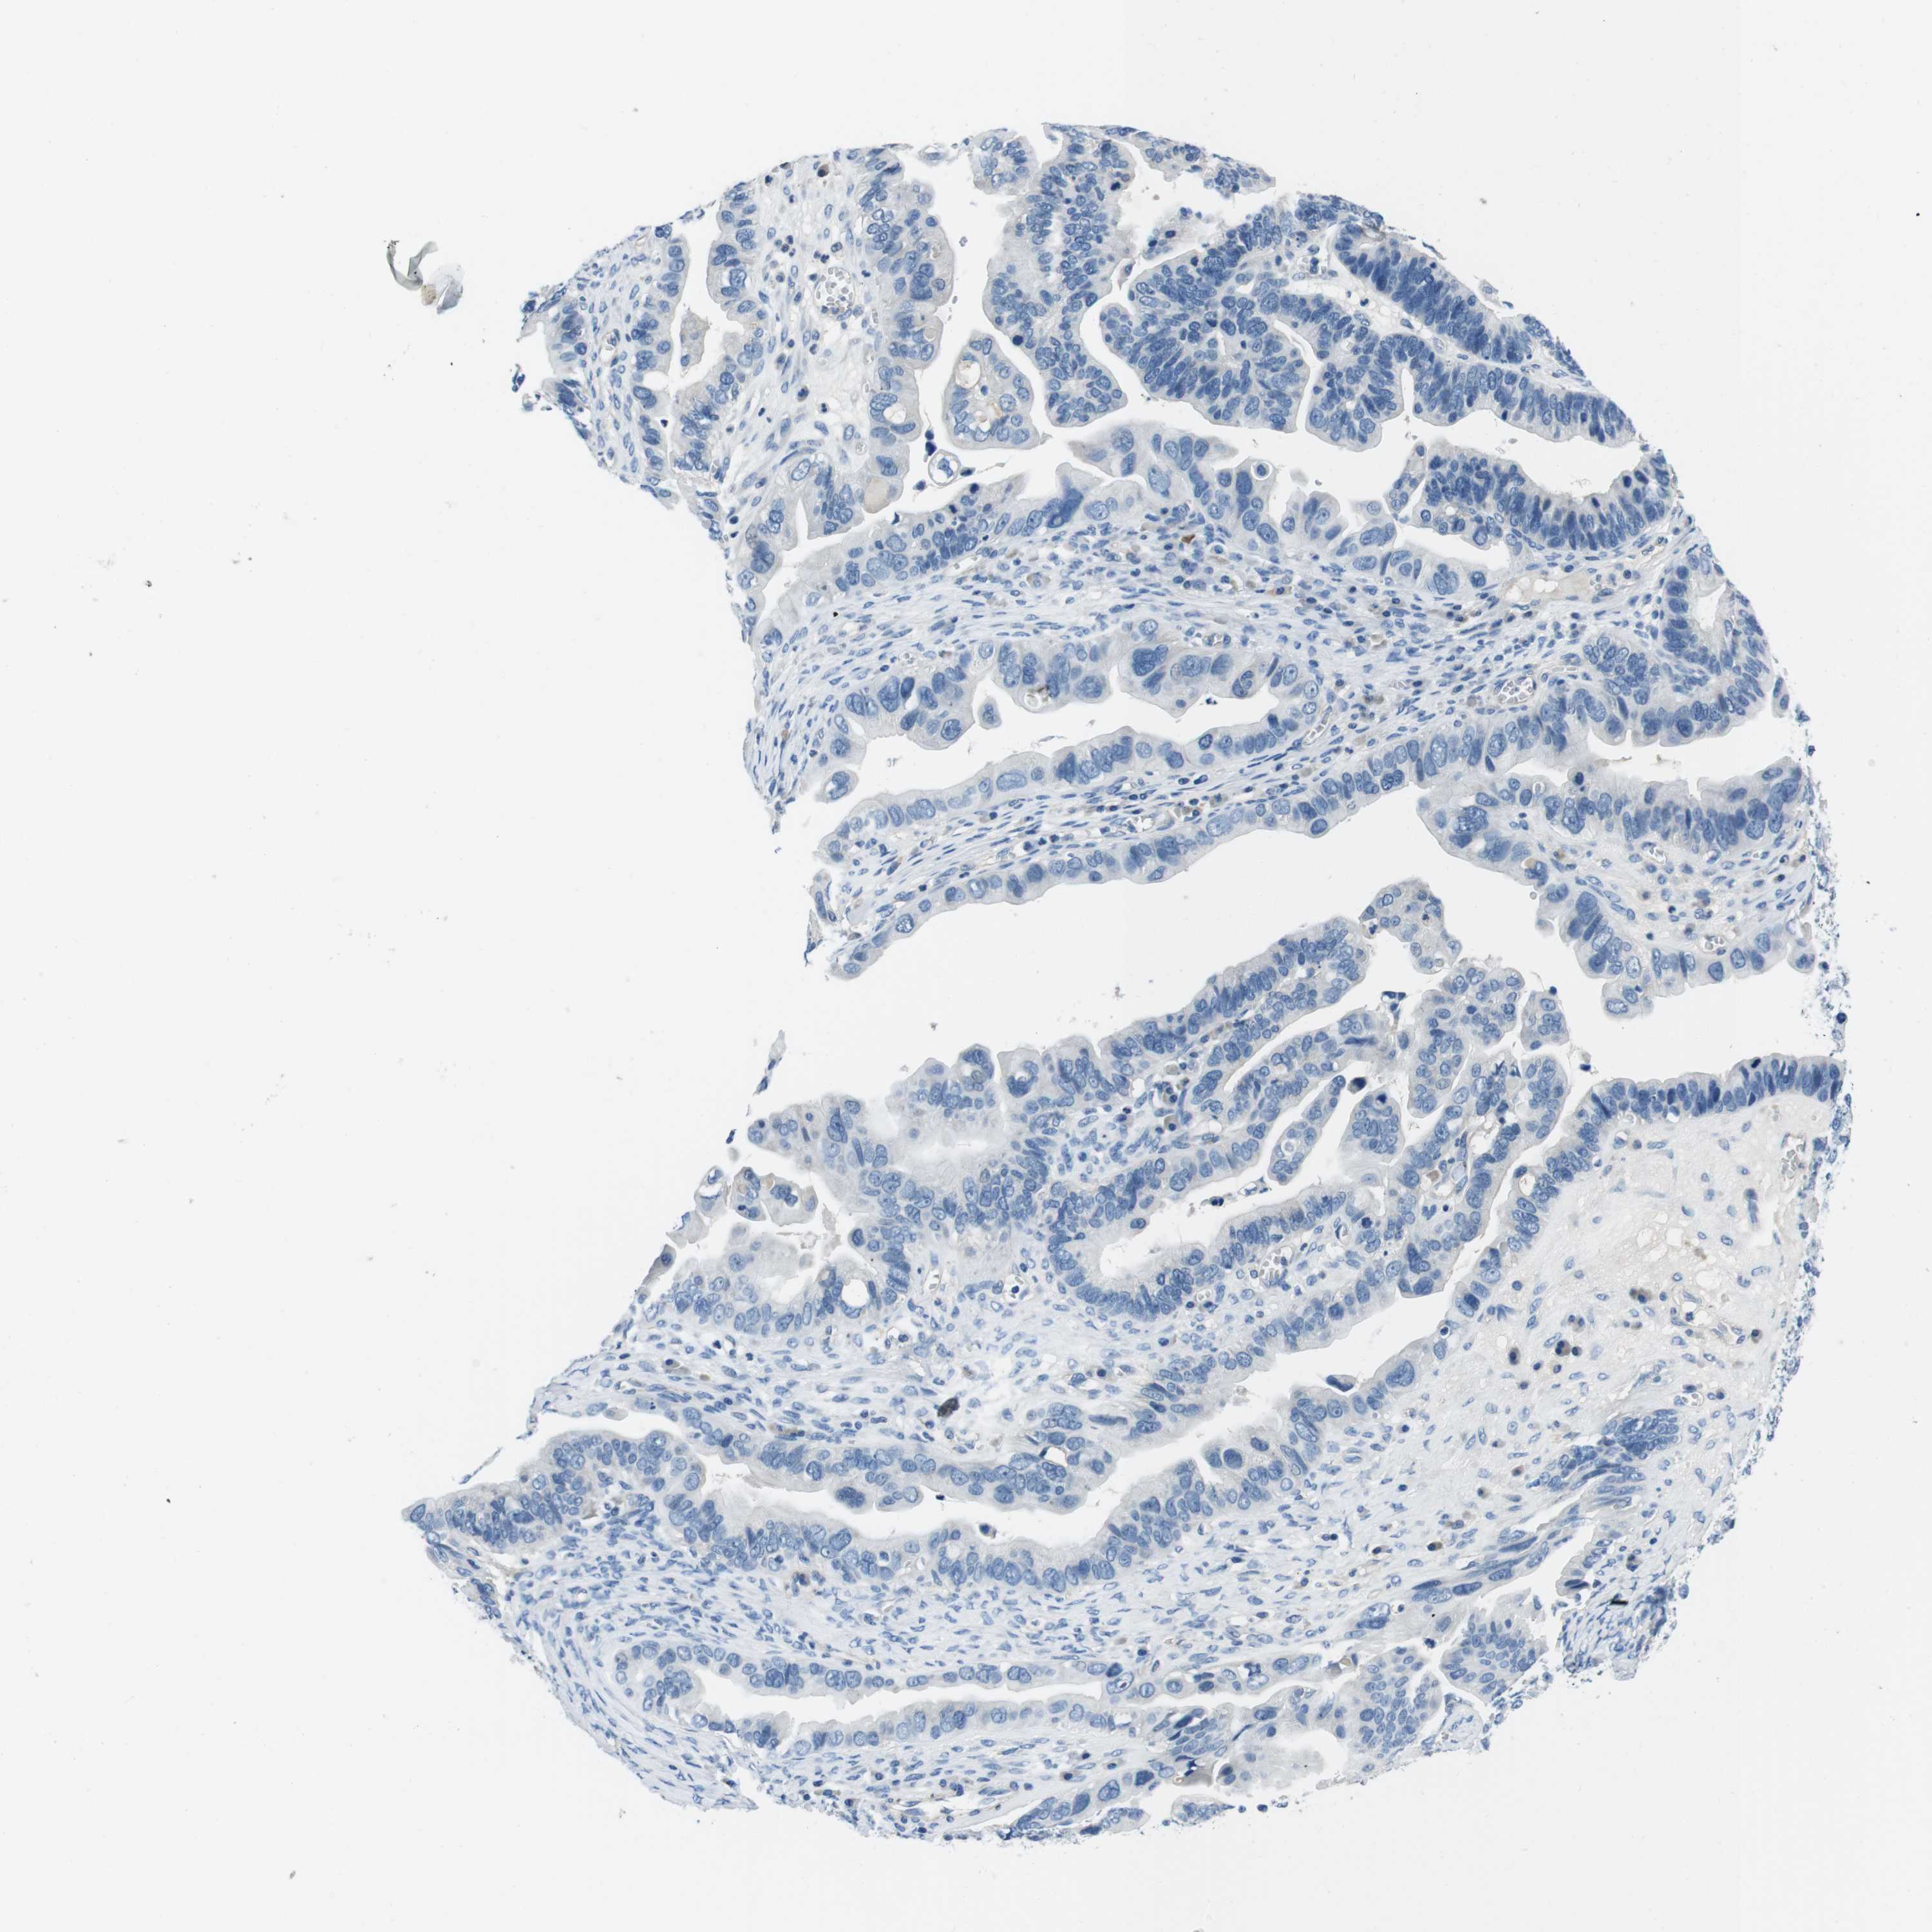

OVARIAN CANCER - Protein expressioni

A mouse-over function shows sample information and annotation data. Click on an image to view it in a full screen mode. Samples can be filtered based on level of antibody staining by selecting one or several of the following categories: high, medium, low and not detected. The assay and annotation is described here.

Note that samples used for immunohistochemistry by the Human Protein Atlas do not correspond to samples in the TCGA dataset.

Antibody stainingi

Antibody staining in the annotated cell types in the current human tissue is reported as not detected, low, medium, or high, based on conventional immunohistochemistry profiling in selected tissues. This score is based on the combination of the staining intensity and fraction of stained cells.

Each image is clickable and will lead to virtual microscopy that enables deeper exploration of all samples and also displays staining intensity scores, fraction scores and subcellular localization as well as patient and tissue information for each sample.

Antibody HPA007845

Staining

High

Medium

Low

Not detected

Cystadenocarcinoma, serous, NOS

Carcinoma, endometroid

Cystadenocarcinoma, mucinous, NOS

Carcinoma, NOS